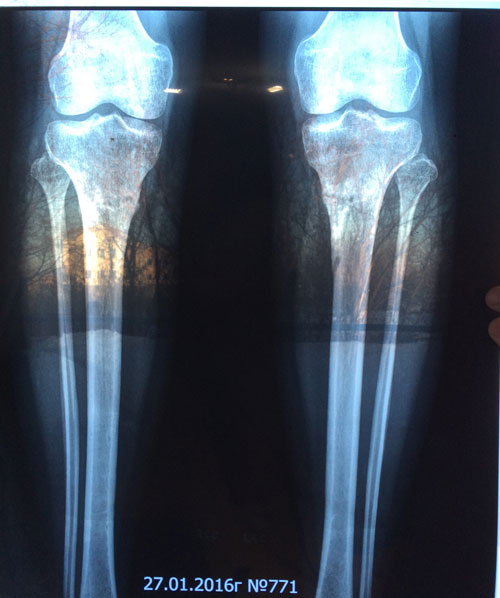

Дата операции 08.10.2015г.

Дата снятие аппаратов 11.12.2015г.

Срок лечения 62 дня.